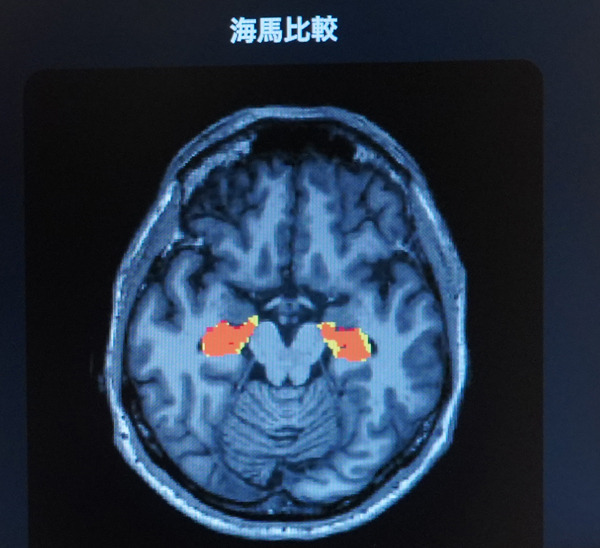

「5年後、認知機能に影響する脳の海馬はどれだけ萎縮する?」ドコモが将来の脳画像を予測する生成AIを開発 海馬の体積変化を可視化 2枚目の写真・画像

「5年後、認知機能に影響する脳の海馬はどれだけ萎縮する?」ドコモが将来の脳画像を予測する生成AIを開発 海馬の体積変化を可視化